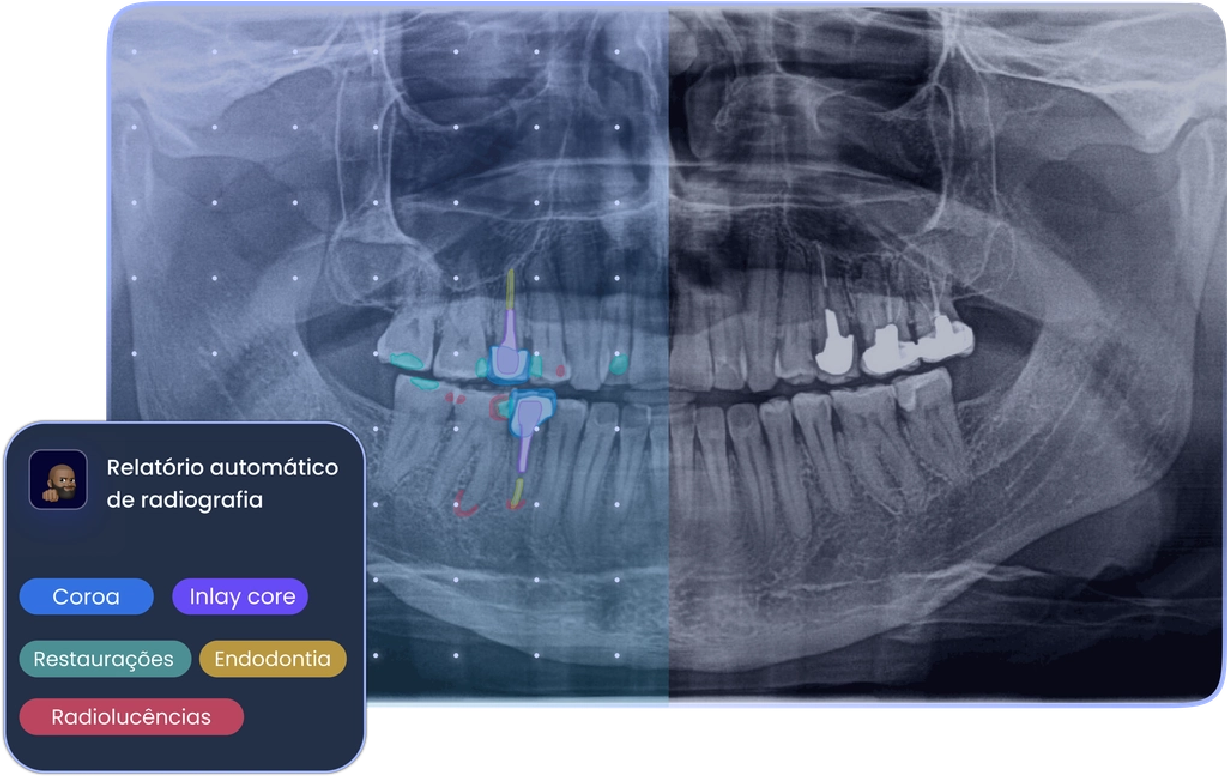

A Allisone posiciona-se como uma solução de apoio ao diagnóstico dentário com IA, com funcionalidades como análise de radiografias 2D, relatórios automáticos, criação de planos de tratamento e relatórios pós-consulta para o paciente.

A plataforma utiliza elementos visuais e códigos de cor para tornar a radiografia mais compreensível, facilitando a explicação do diagnóstico e do plano de tratamento.

Entre as funcionalidades destacadas pela Allisone estão o relatório radiológico automático, a emissão de relatório pós-consulta e a criação automática de planos de tratamento.

A Allisone permite interpretar radiografias 2D e identificar elementos clínicos relevantes de forma assistida.